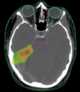

Whole brain radiation

Whole brain radiotherapy (WBRT) is a palliative option for patients with brain metastases that alleviates symptoms, decreases the use of corticosteroids needed to control tumor-associated edema, and potentially improves overall survival. It has been reported to increase the risk of cognitive decline. [Source: Wikipedia ]